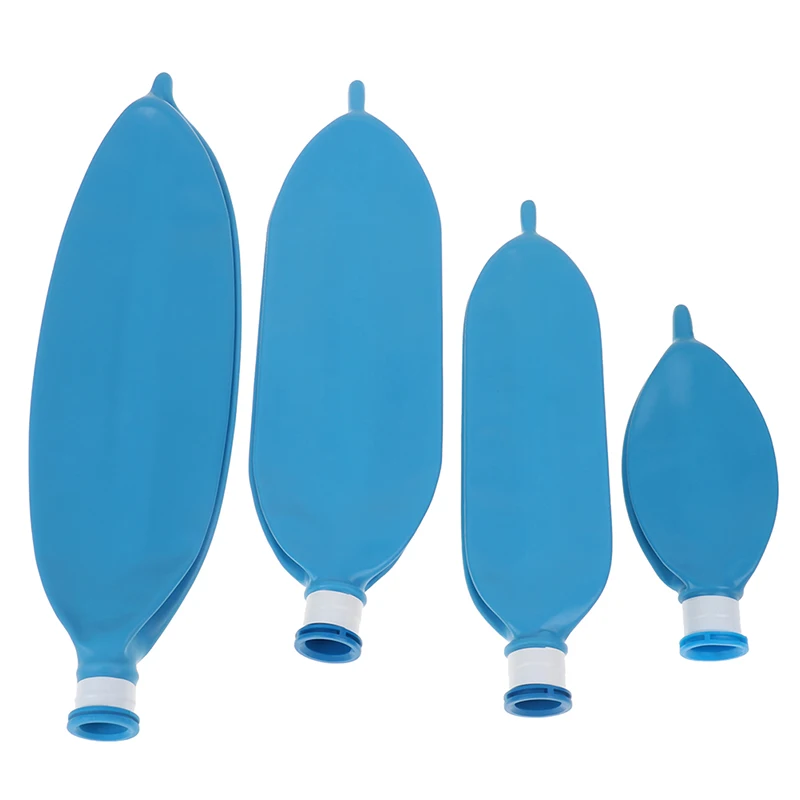

Латексный одноразовый дыхательный аппарат для анестезии объемом л, 1 л, 2 л, 3 л

Описание:Материал: латексРазмер: 0.5л 1Л 2л 3лЦвет: синий